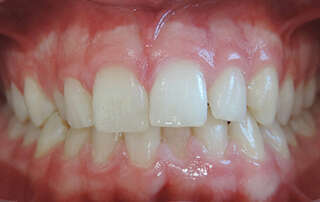

CANINES INCLUSES